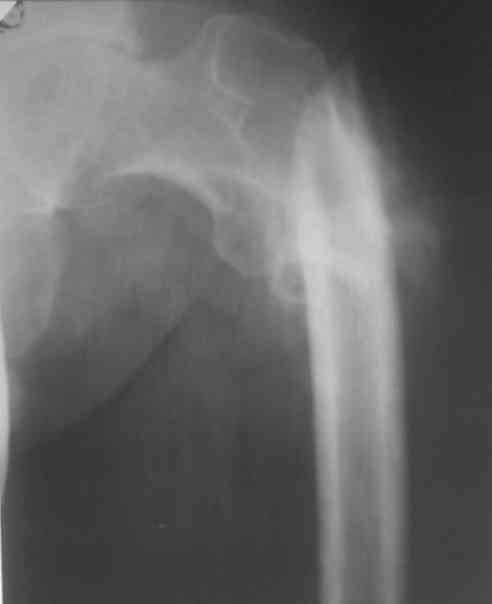

Больной 48 лет, 1,5 года с момента травмы!!Лечился в местной больнице

скелетным вытяжением в течение 2 месяцев!!Поступил для оперативного

лечения. Выраженное укорочение конечности на 10 см., с наружной

ротацией,С патологической подвижностью.

Уважаемые коллеги - что вы предложите для Коррекции перелома и

устранения ложного сустава, и  какие виды операций для устранения

укорочения!!Какой метод фиксации? С уважением!!!!